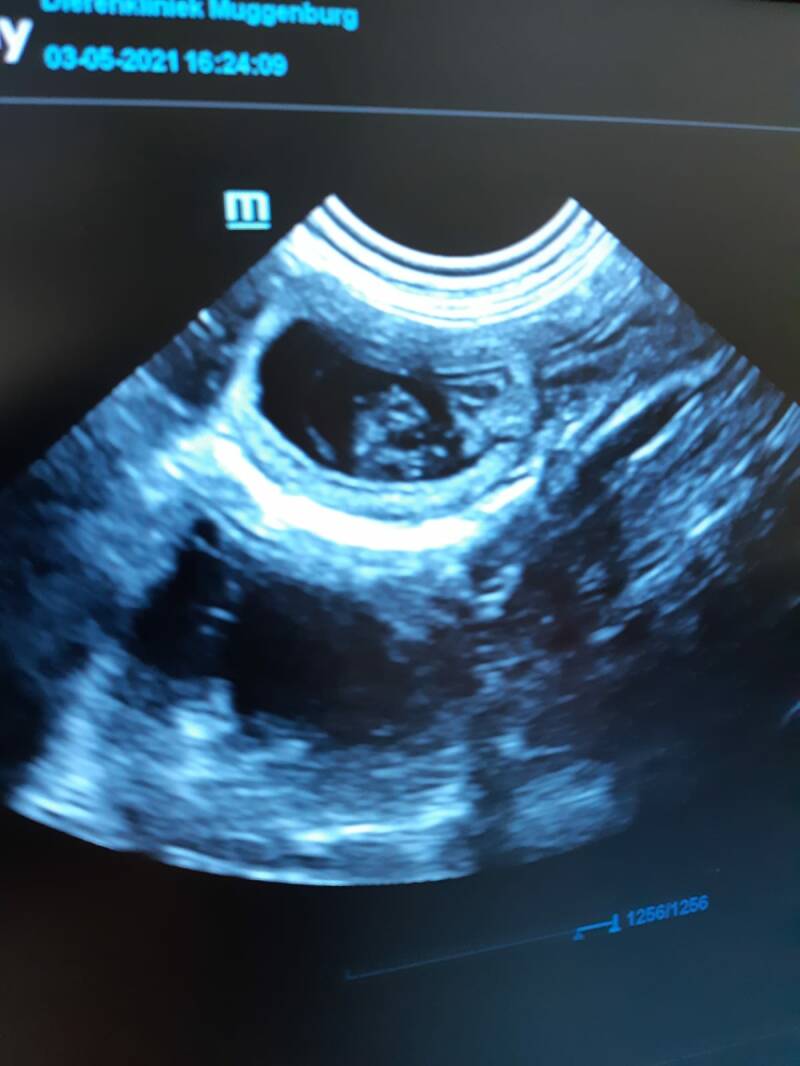

03-05-2021

We zijn vandaag bij de dierenarts geweest en hebben een echo laten maken vorige keer was het niet gelukt en bleek Lois leeg te zijn. Gelukkig mogen we nu vertellen dat lois 4 kittens mag verwachten de hartjes waren goed te horen. Ook vond de dierenarts een leeg vruchtzakje die zich niet heeft ontwikkeld